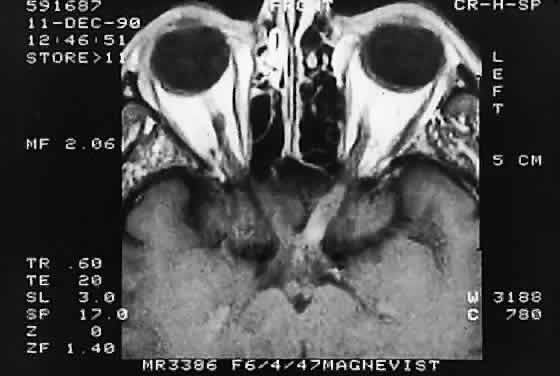

Computed tomographic (CT) and magnetic resonance imaging (MRI) have had a significant impact on the management of patients.29 Many tumors are diagnosed based on imaging features alone, without tissue confirmation (Fig. 35). They typically show a demarcated fusiform enlargement of the nerve, which may be kinked and indent the globe. On T2-weighted MRI, a circumferential component surrounds a compact core of low signal intensity.23 MRI is particularly useful in assessing the extent of the lesion.

Fig. 35. Computed tomographic scan showing left optic nerve glioma.